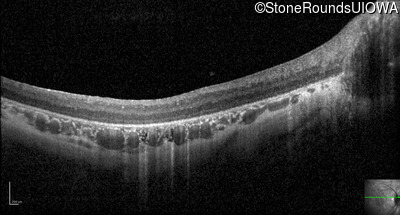

Optical Coherence Tomography - Left - 20/500 sc

Exemplar / OCT Stack